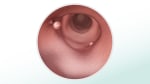

Los procedimientos con los que se puede observar el interior del colon y encontrar los pólipos incluyen la colonoscopia, la sigmoidoscopia flexible y la colonografía por tomografía computarizada (colonoscopia virtual). Los pólipos que se encuentran durante una colonoscopia a menudo pueden extraerse durante la prueba. Si se detectan pólipos durante uno de los otros procedimientos, usted puede necesitar una colonoscopia.